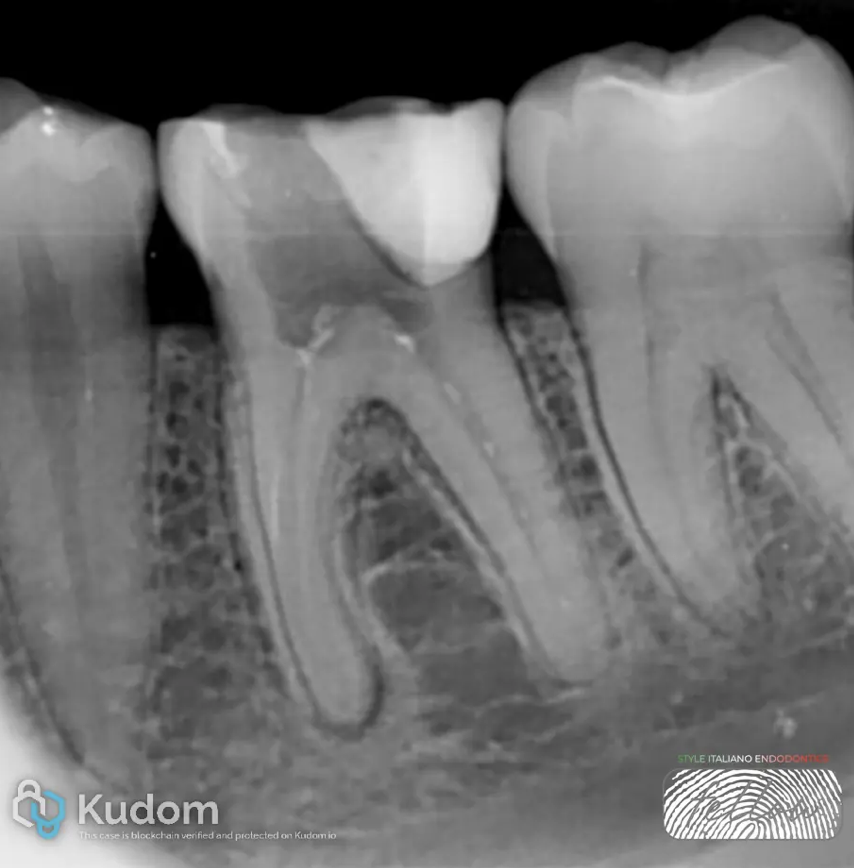

Final Irrigation: The canals were irrigated with EDTA 17% for one minute to remove the smear layer, followed by a final rinse with saline solution.

Obturation: The continuous wave of condensation technique was used for root canal filling.

Coronal Seal: Sterile Teflon and glass ionomer cement were placed as a provisional coronal seal.

Fig. 6